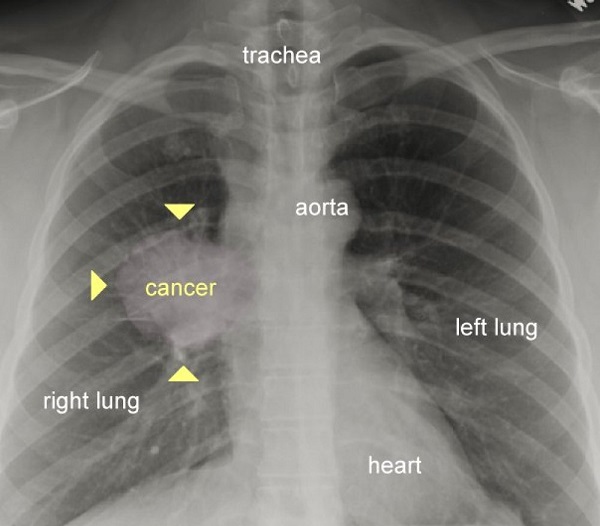

سرطان ریه

در این تصویر نقطه سرطانی در ریه به خوبی قابل مشاهده است. یک ریه سالم فاقد هر گونه تاری یا نقاط بزرگ است.